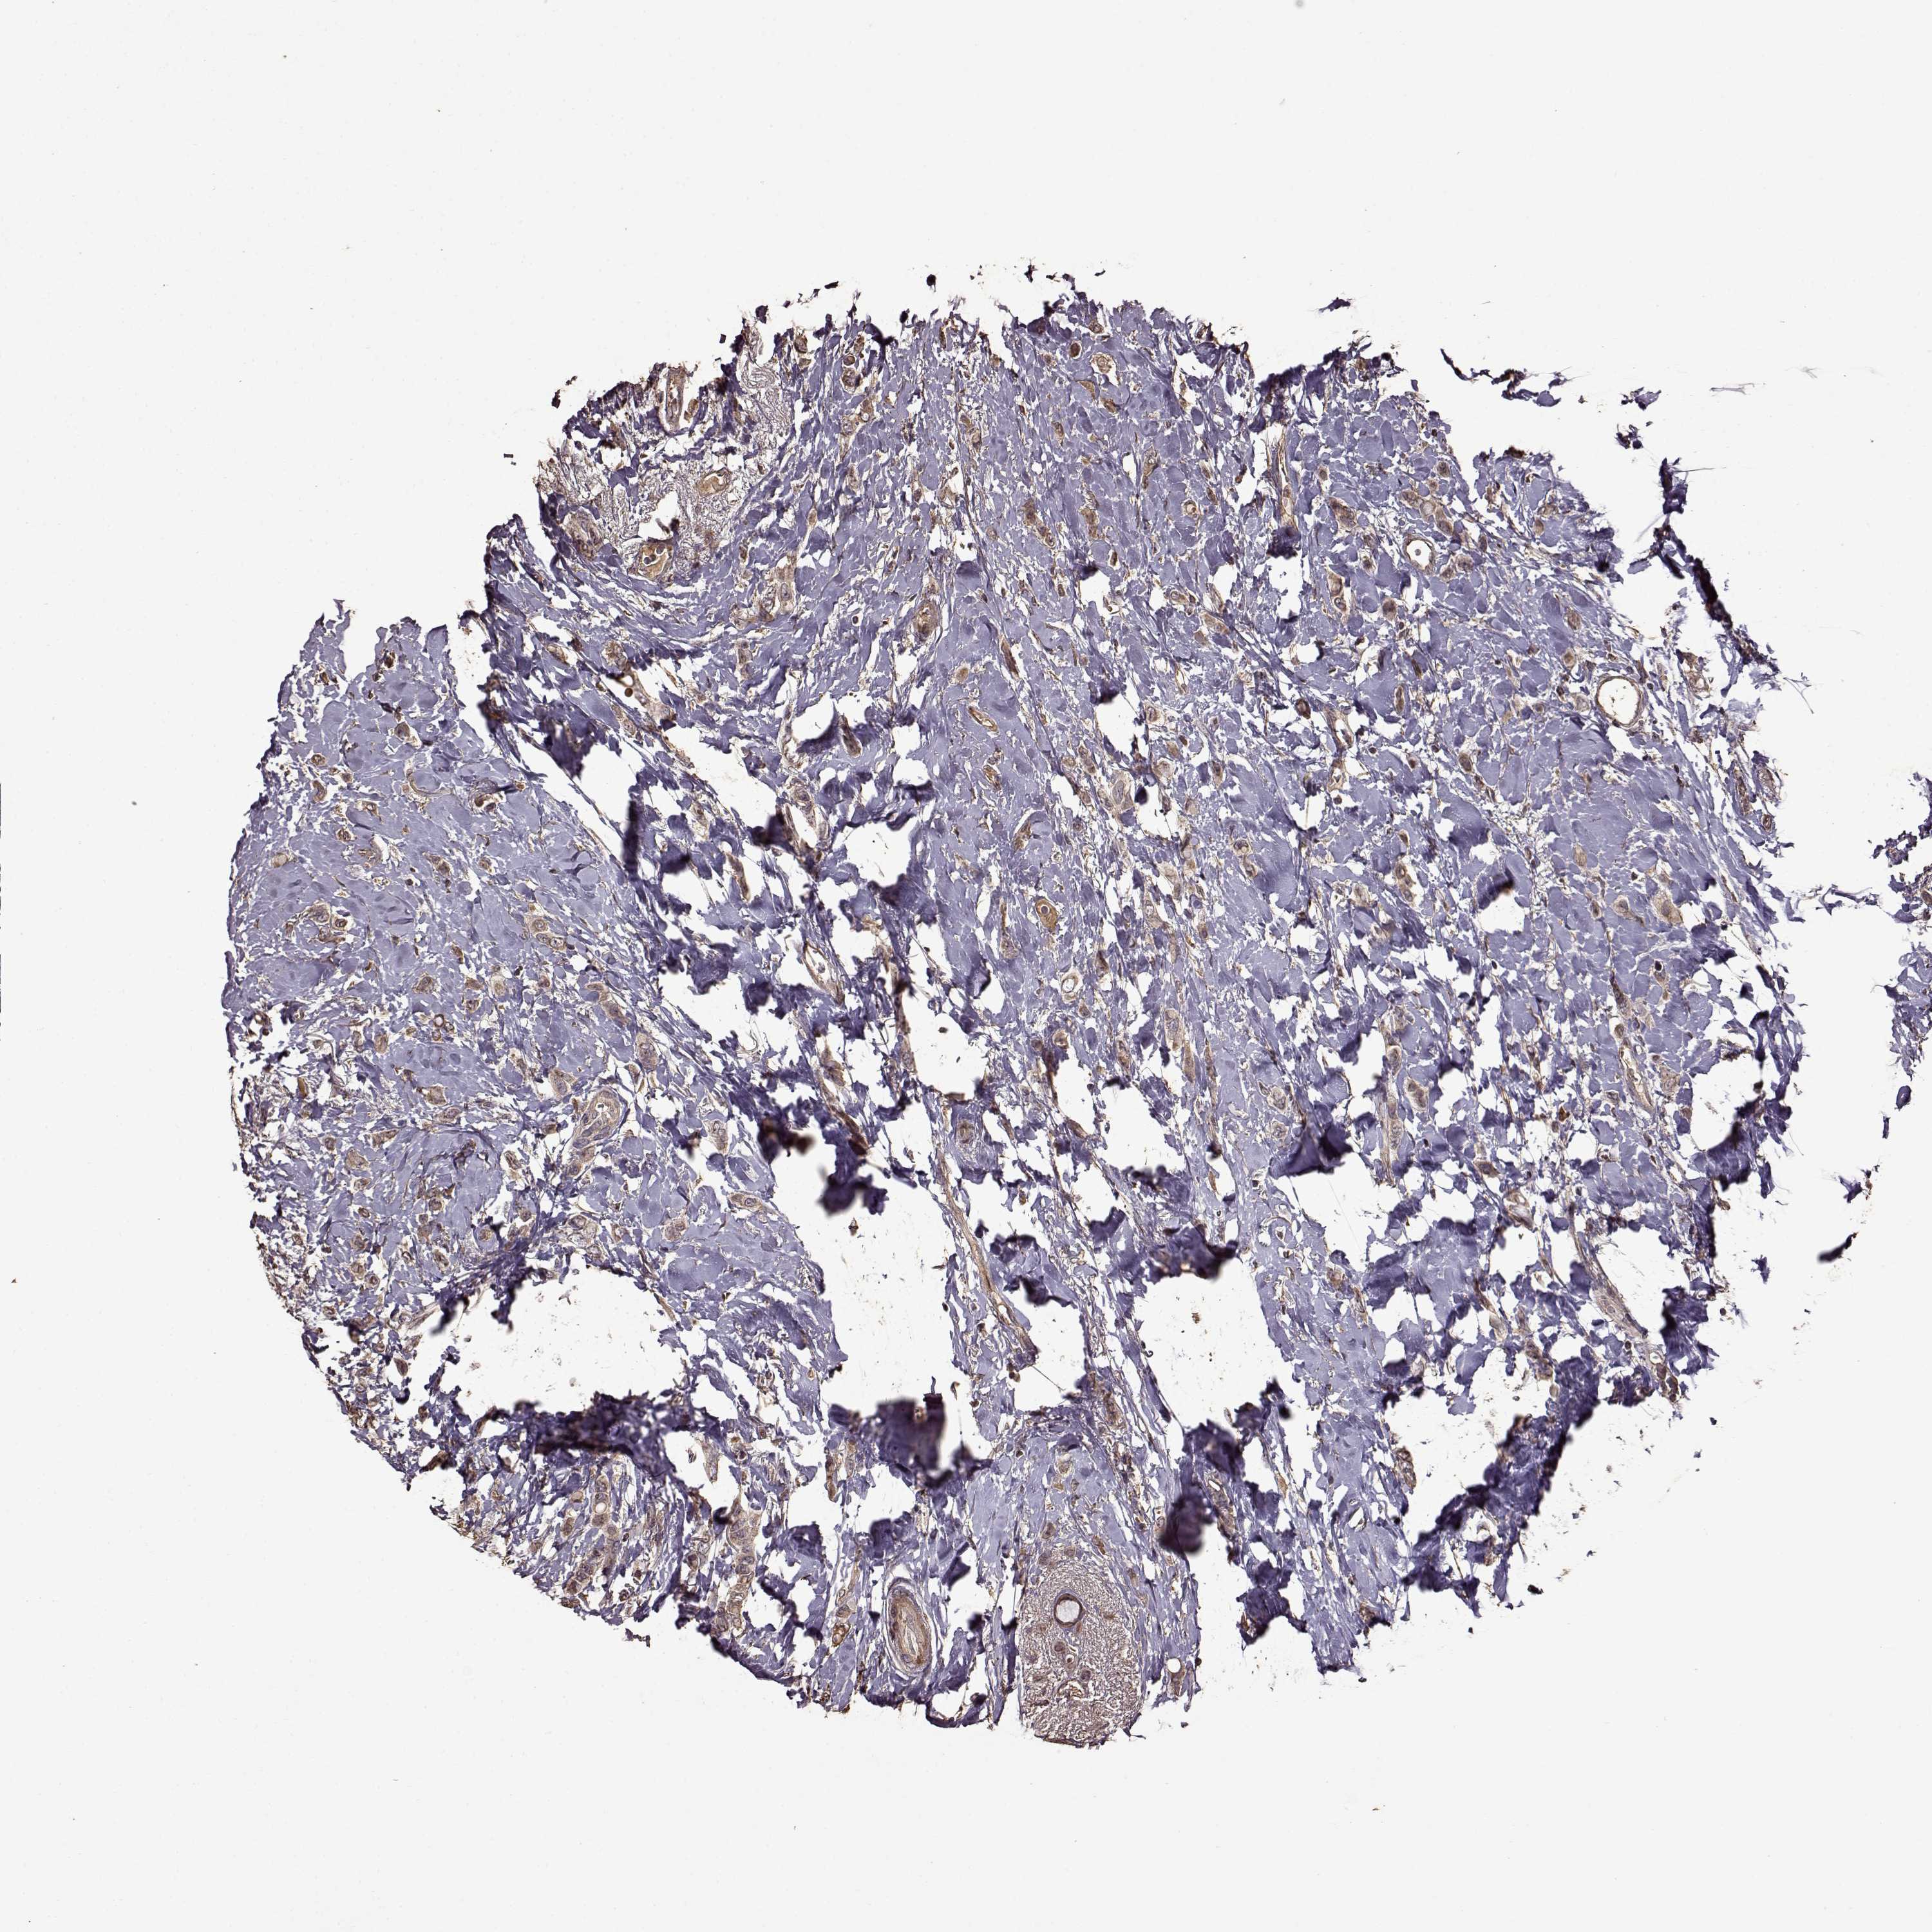

CANCER BREAST CANCER Show tissue menu

BRCA TCGA BRCA VALIDATION PROTEIN EXPRESSION